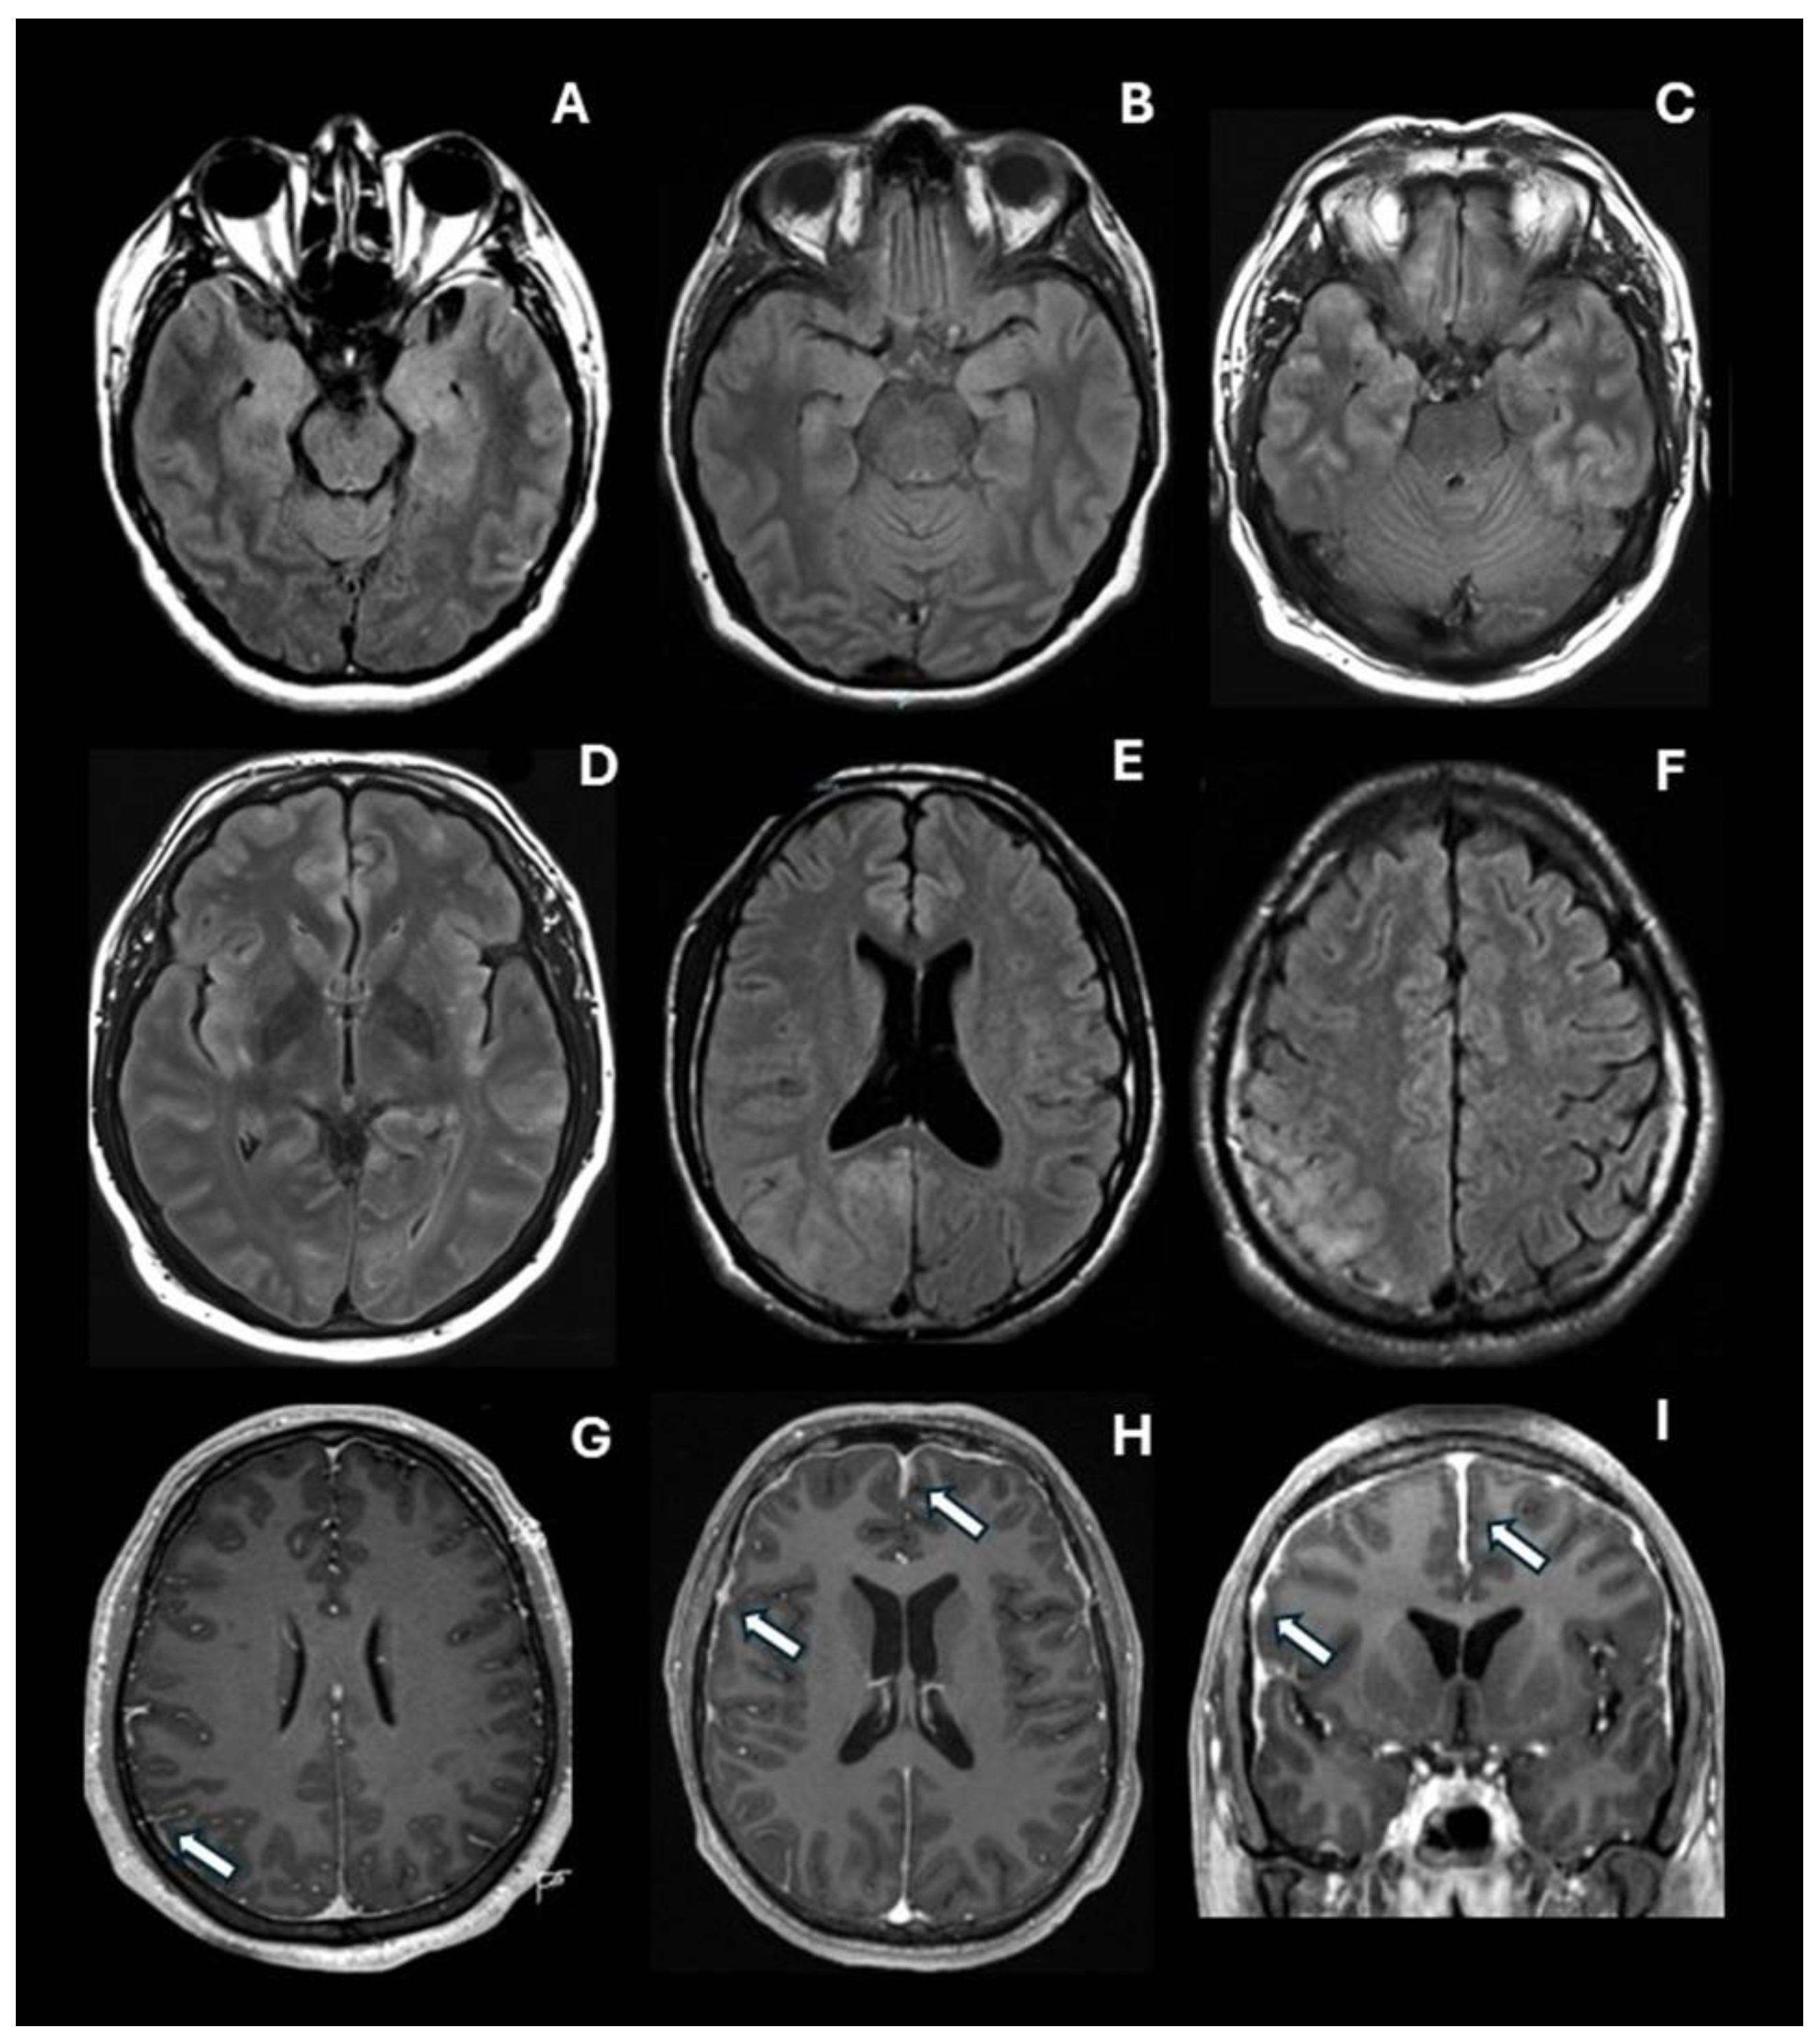

3.3. The Assessment of Brain MRI Findings

| Abnormal MRI | 65 (56.5%) | 31 (27.0%) | 2.10 | 1.49 – 2.95 | <0.001* |

| ABNORMALITIES IN LIMBIC AND PARALIMBIC STRUCTURES | |||||

| Medial temporal lobe | 64 (55.7%) | 30 (26.1%) | 2.13 | 1.51 – 3.02 | <0.001* |

| Right amygdala | 41 (35.7%) | 21 (18.3%) | 1.95 | 1.23 – 3.09 | 0.003 |

| Left amygdala | 44 (38.3%) | 20 (17.4%) | 2.20 | 1.39 – 3.49 | <0.001* |

| Right hippocampus | 51 (44.3%) | 26 (22.6%) | 1.96 | 1.32 – 2.91 | <0.001* |

| Left hippocampus | 53 (46.1%) | 26 (22.6%) | 2.04 | 1.38 – 3.02 | <0.001* |

| Right parahippocampal gyrus | 27 (23.5%) | 12 (10.4%) | 2.25 | 1.20 – 4.22 | 0.008 |

| Left parahippocampal gyrus | 32 (27.8%) | 19 (16.5%) | 1.68 | 1.02 – 2.79 | 0.039 |

| Right insular cortex | 36 (31.3%) | 15 (13.0%) | 2.40 | 1.39 – 4.14 | 0.001 |

| Left insular cortex | 46 (40.0%) | 18 (15.7%) | 2.56 | 1.58 – 4.13 | <0.001* |

| Right anterior cingulate cortex | 51 (44.3%) | 19 (16.5%) | 2.68 | 1.70 – 4.25 | <0.001* |

| Left anterior cingulate cortex | 49 (42.6%) | 20 (17.4%) | 2.45 | 1.56 – 3.85 | <0.001* |

| Right middle cingulate cortex | 31 (27.0%) | 14 (12.2%) | 2.21 | 1.25 – 3.94 | 0.005 |

| Left middle cingulate cortex | 28 (24.3%) | 13 (11.3%) | 2.15 | 1.18 – 3.94 | 0.010 |

| Right posterior cingulate cortex | 28 (24.3%) | 9 (7.8%) | 3.11 | 1.54 – 6.30 | 0.001 |

| Left posterior cingulate cortex | 26 (22.6%) | 10 (8.7%) | 2.60 | 1.31 – 5.14 | 0.004 |

| ABNORMALITIES IN NEOCORTICAL STRUCTURES | |||||

| Right dorsolateral prefrontal cortex | 44 (38.3%) | 20 (17.4%) | 2.20 | 1.39 – 3.49 | <0.001* |

| Left dorsolateral prefrontal cortex | 42 (36.5%) | 21 (18.3%) | 2.00 | 1.27 – 3.15 | 0.002 |

| Right orbitofrontal cortex | 24 (20.9%) | 10 (8.7%) | 2.40 | 1.16 – 4.97 | 0.009 |

| Left orbitofrontal cortex | 25 (21.7%) | 8 (7%) | 3.13 | 1.47 – 6.64 | 0.001 |

| Right lateral temporal cortex | 39 (33.9) | 25 (21.7%) | 1.56 | 1.01 – 2.40 | 0.039 |

| Left lateral temporal cortex | 49 (42.6%) | 21 (18.3%) | 2.33 | 1.50 – 3.63 | <0.001* |

| Right parietal cortex | 45 (39.1%) | 18 (15.7%) | 2.50 | 1.54 – 4.05 | <0.001* |

| Left parietal cortex | 44 (38.3%) | 16 (13.9%) | 2.75 | 1.65 – 4.58 | <0.001* |

| Right occipital cortex | 46 (40.0%) | 11 (9.6%) | 4.18 | 2.28 – 7.66 | <0.001* |

| Left occipital cortex | 42 (36.5%) | 12 (10.4%) | 3.50 | 1.95 – 6.30 | <0.001* |

| ABNORMALITIES IN OTHER SUBCORTICAL STRUCTURES | |||||

| Right thalamus | 6 (5.0%) | 0 (0%) | ∞ | Not estimable | 0.013 |

| Left thalamus | 7 (6.1%) | 2 (1.7%) | 3.50 | 0.74 – 16.49 | 0.089 |

| Right striatum | 7 (6.1%) | 1 (0.9%) | 7.00 | 0.88 – 55.99 | 0.031 |

| Left striatum | 8 (7.0%) | 1 (0.9%) | 8.00 | 1.02 – 62.94 | 0.017 |

| Brainstem | 8 (7.0%) | 1 (0.9%) | 8.00 | 1.02 – 62.94 | 0.017 |

| Cerebellum | 10 (8.7%) | 1 (0.9%) | 10.00 | 1.30 – 76.86 | 0.005 |

| MENINGEAL ABNORMALITIES | |||||

| Meningeal enhancement | 32 (27.8%) | 12 (10.4%) | 2.67 | 1.45 – 4.91 | 0.001 |

| Pachymeningeal enhancement | 30 (26.1%) | 12 (10.4%) | 2.50 | 1.35 – 4.64 | 0.002 |

| Leptomeningeal enhancement | 5 (4.3%) | 0 (0%) | ∞ | Not estimable | 0.024 |